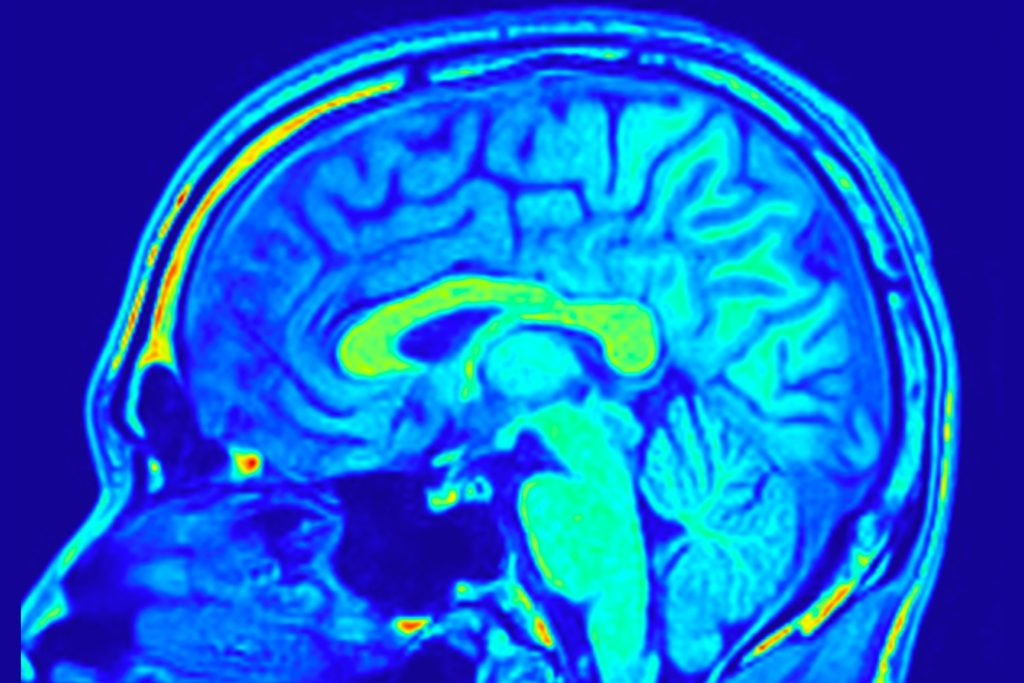

The human brain continues to surprise scientists. From how it learns to the fact that our brains glow

The human brain continues to surprise scientists. From how it learns to the fact that our brains glow, there’s a lot we have yet to learn about the inner workings of the human brain. One especially surprising thing, though, is that the brain doesn’t appear to see exactly what you see. Instead, scientists say the brain sees what it expects to see.According to scientists, the way that the brain interprets the data our eyes send it is very intriguing. Instead of waiting to see exactly how a scene plays out, your brain actually predicts what will happen. So, for instance, if you see a friend reaching for a pot, your brain interprets that their hand will reach the pot and grab onto the handle.

In most cases, it’s correct. Though, of course there can always be split section changes, which can result in how the brain sees not quite adding up to what really happens. The basis of this phenomenon is driven by what researchers call the action observation network, or AON. This is a set of brain regions that become active whenever you watch someone else interact with something.

This setup has been confirmed by scientists over the course of decades, using snippets of data captured from a multitude of different lab tests. But those snippets, usually one- to two-second videos, don’t show the entire picture. That’s why a more recent study published in Cell Reports is based on research that wanted to dig deeper. More specifically, with this new research, the scientists wanted to answer whether or not the pipeline of information changes when the viewer can already forecast the next step in the process.To test this, and to test how the brain actually sees, the researchers set up two different versions of everyday scenes. In the natural scene, the actions played out exactly as expected. However, in the second scene, they scrambled the clips and then had volunteers watch both while recording their brain activity. Some of the participants were already implanted with intracranial electrodes for medical monitoring, too, so they were also able to capture electrical signals found deep inside the cortex with extreme precision.

The researchers found that the brain worked exactly as expected when the order of clips in the scene made sense. The data even showed that when the brain could forecast what would happen next, it actually used its visual areas less. However, when the more jumbled cut played out, the data showed how the brain sees changes is based on whether or not it can properly forecast what will happen next.

Since the clips were more jumbled and out of order, the brain couldn’t properly determine what the next step in the process was, leading to more activity in other areas of the brain. These results also hint that our motor memories could play a prime role in how our brain handles the data that our eyes feed to it. Essentially, our brains use memory to see.

While the entire idea here might seem a bit silly and even risky, the fact that the brain doesn’t need to use its full power to see how a scene will play out is a prime example of just how efficient the human brain is. There’s a reason that scientists are looking for ways to use brain cells in computers, because the brain is extremely efficient and powerful.